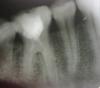

Мария КЧЁ Опубликовано 4 июня, 2010 Автор Поделиться Опубликовано 4 июня, 2010 первый снимок, до чистки каналов у Врача, больше снимков нет Ссылка на комментарий

Мария КЧЁ Опубликовано 11 июня, 2010 Автор Поделиться Опубликовано 11 июня, 2010 вот снимки перед пломбированием зуба. подскажите пожалуйста, мне было больно при засововании инструмента в один из каналов, можно ли было пломбировать? По-моему что-то не так с каналами, и с корнем, на снимке какое-то почернение. Ссылка на комментарий

Мария КЧЁ Опубликовано 11 июня, 2010 Автор Поделиться Опубликовано 11 июня, 2010 спасибо большое за совет. А глубже не дала, у меня паника от боли была. так каналы повреждены? на снимке как-то не ровно канал идет, прерывается, потом где-то начинается.Подскажите, может знаете в г. Волгограде эндодонтиста?А если так как есть оставить чем это грозит? Ссылка на комментарий

Scrabble Опубликовано 11 июня, 2010 Поделиться Опубликовано 11 июня, 2010 Снимки до вмешательства оптимистичны-а после есть? Ссылка на комментарий